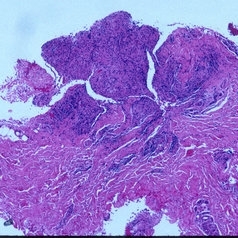

Sarcoidosis Panuveitis Slide 8

Biopsy of one of the sub-cutaneous nodules revealed non-caseating granulomas consistent with sarcoidosis.

Photographer: The New York Eye & Ear Infirmary Department of Pathology and Laboratory Medicine

Condition/keywords: sarcoidosis panuveitis